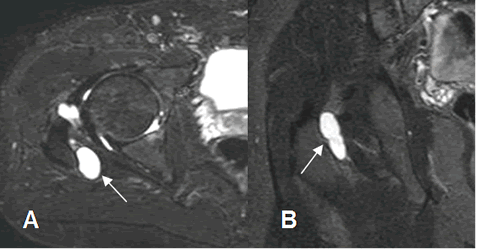

Fig 138. Bursitis.

A: RM axial y B: RM coronal en STIR. Imagen ovalada y de consistencia quística en relación con el músculo obturador interno, por bursitis.